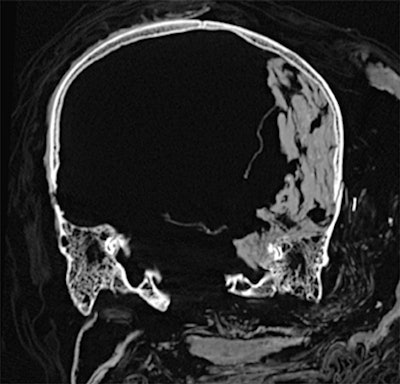

Dr. Sahar Saleem, a professor of radiology at Cairo University who specializes in CT mummy imaging, and archeologist Zahi Hawass, PhD, have used CT scans and 3D reconstructions to suggest he had multiple killers. They have presented their findings in an article published on 17 February in Frontiers of Medicine that received over 10,500 page views by February 21.

CT revealed details of the head injuries, including wounds that had not been discovered in previous examinations and had been skillfully hidden by the embalmers. The mummy's deformed hands indicate that Seqenenre may have been captured on the battlefield, and his hands were tied behind his back, preventing him from deflecting the fierce attack on his head.

The CT scans, combined with other evidence, suggest the execution was carried out by multiple attackers, which the scientists confirmed by studying five different Hyksos weapons that matched the king's wounds. The study also determined that Seqenenre was about 40 when he died, based on the detailed morphology revealed in the images, providing the most precise estimate to date, according to the authors.

In addition, the investigation revealed details about the mummification of Seqenenre's body. For instance, the embalmers used a sophisticated method to hide the king's head wounds under a layer of embalming material that functioned similarly to the fillers used in modern plastic surgery. This would imply that mummification took place in a real mummification laboratory rather than in a poorly equipped place, as previously interpreted.

Saleem examined the mummy on May 4, 2019. She said she used the usual optimum CT scan parameters, including field-of-view and slice thickness, to provide the best 3D reconstruction. Because of the COVID-19 pandemic, it took several weeks to study the Hyksos weapons stored at the Cairo Egyptian Museum and to correlate them with the injuries by physical inspection of the mummy and on CT scans.